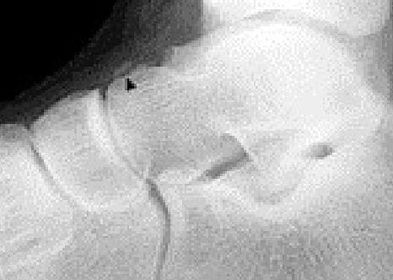

| What is this? What is shown by A and B? | STJ coalition A = talar neck spurring B = Halo or 'C' sign |

| What is this? | Posterior talocalcaneal coalition |